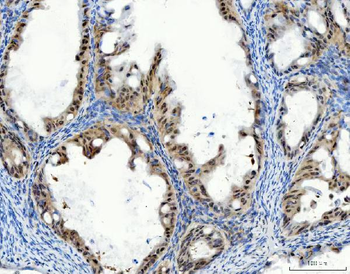

10 μg, 100 μgChemerin Rabbit Polyclonal Antibody [orb156351]

IF, IHC-Fr, IHC-P

Bovine, Porcine

Human, Mouse, Rabbit, Rat

Rabbit

Polyclonal

Unconjugated

100 μl, 200 μl, 50 μlGoat anti-CYP26B1 Antibody [orb19329]